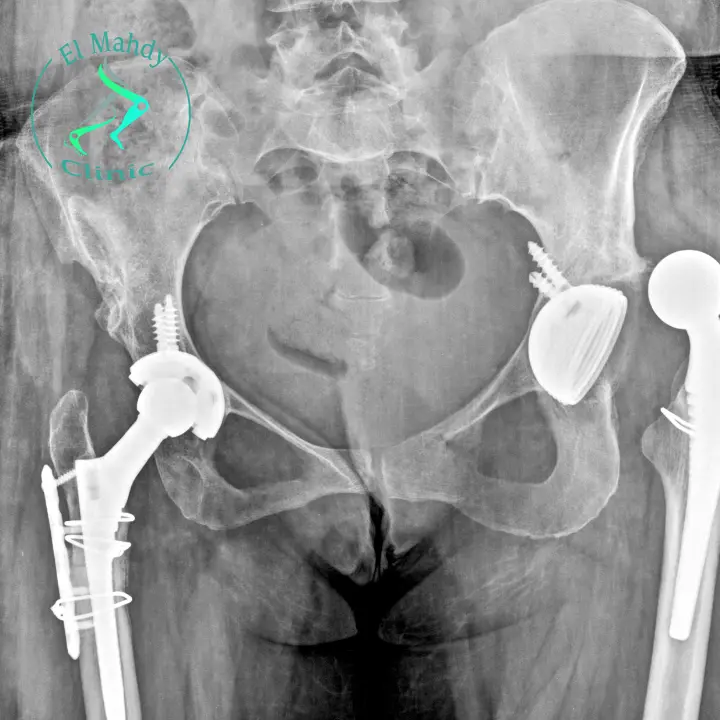

يعد مفصل الورك الصناعي حلًا فعالًا للمرضى الذين يعانون من مشكلات شديدة في مفصل الورك، حيث يساعد في استعادة الحركة وتخفيف الألم. ولكن، يعد من عيوب مفصل الورك الصناعي أنه قد يحدث خلع في المفصل، مما يؤدي إلى ظهور أعراض خلع مفصل الورك الصناعي بشكل واضح، حيث يعاني المريض من ألم شديد وأعراض أخرى.

وفي هذه المقالة، سنوضح ما هي أعراض خلع مفصل الورك الصناعي وأسباب خلعه، وكيف يمكن علاج الخلع.